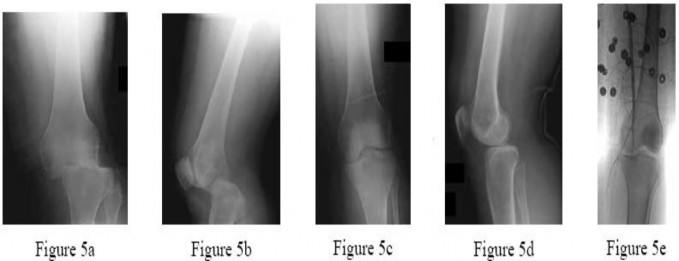

Bone morphogenetic proteins (BMPs) play a critical role in osteoinduction and bone healing. Recombinant human BMP-2 (rhBMP-2) is utilized in various spine and orthopedic trauma procedures. Upon binding to its transmembrane serine/threonine kinase receptor, which intracellular signaling pathway is primarily activated by BMP-2?

Options:

- Smad 2 and 3

- Smad 1, 5, and 8

- Wnt/Beta-catenin

- MAP kinase (MAPK)

- JAK/STAT

Correct Answer: Smad 1, 5, and 8

Explanation:

BMP-2 and BMP-7 act via cell surface receptors that have intrinsic serine/threonine kinase activity. Once activated, these receptors phosphorylate the intracellular R-Smads (Receptor-regulated Smads), specifically Smad 1, Smad 5, and Smad 8. These complex with Co-Smad (Smad 4) to translocate to the nucleus and induce osteogenic gene transcription. Smad 2 and 3 are primarily associated with the TGF-beta signaling pathway, not BMP.

Question 30:

A 45-year-old male is struck by a vehicle and sustains a complex tibial plateau fracture. The injury is classified as a Schatzker Type IV fracture. What is the classic mechanism of injury, and which surgical approach is most commonly required for anatomic reduction and buttressing of this specific pattern?

- Valgus force with axial loading; Anterolateral approach

- Valgus force with axial loading; Posteromedial approach

- Varus force with axial loading; Anterolateral approach

- Varus force with axial loading; Posteromedial approach

- Pure axial loading; Dual (anterolateral and posteromedial) approach

Correct Answer: Varus force with axial loading; Posteromedial approach

Schatzker Type IV represents a medial tibial plateau fracture, classically caused by a high-energy varus force combined with axial loading. Because the medial plateau is dense and strong, this fracture implies high energy and often subluxation/dislocation of the knee joint. The optimal surgical approach involves buttressing the medial fragment, which is best achieved via a posteromedial approach to place an anti-glide or buttress plate.